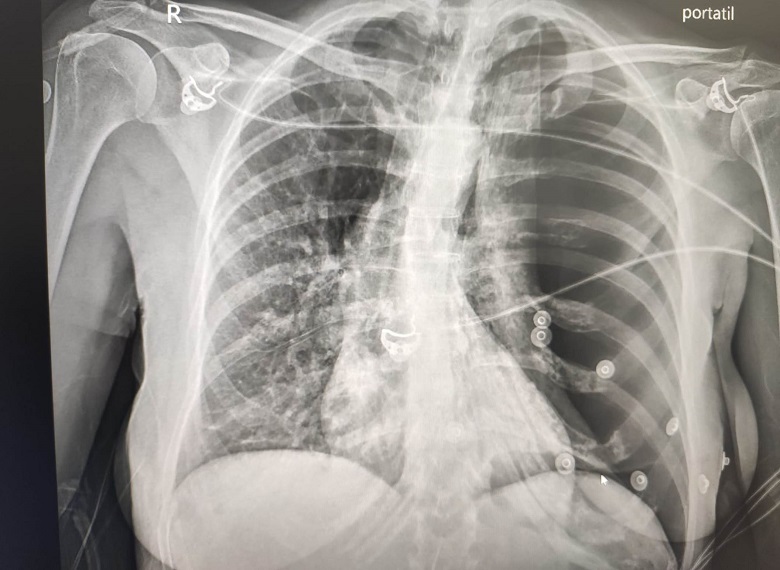

A su llegada al hospital, la paciente persistía con mal estado general, sin cambios en la sintomatología referida previamente. La saturación de oxígeno remontó a 98% tras la administración de oxigenoterapia complementaria (2 L mediante gafas nasales). Se le hizo una analítica por vía urgente con marcadores de daño miocárdico, que resultaron negativos, y radiografía de tórax, en la que se visualizó neumotórax izquierdo masivo a tensión (figura 2). Se avisó a cirugía torácica, que procedió a colocar un drenaje pleural con fuga aérea y a ingresar a la paciente. Después de la evacuación del neumotórax, se le hizo un electrocardiograma de control en el que el segmento ST se había normalizado.